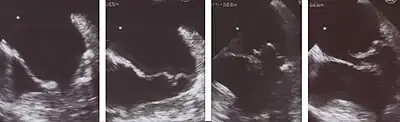

Echocardiography is the most useful method of diagnosing a prolapsed mitral valve. Two- and three-dimensional echocardiography is particularly valuable as they allow visualization of the mitral leaflets relative to the mitral annulus. This allows measurement of the leaflet thickness and their displacement relative to the annulus. Thickening of the mitral leaflets >5 mm and leaflet displacement >2 mm above the annular plane in parasternal long-axis view indicates classic mitral valve prolapse.[35]